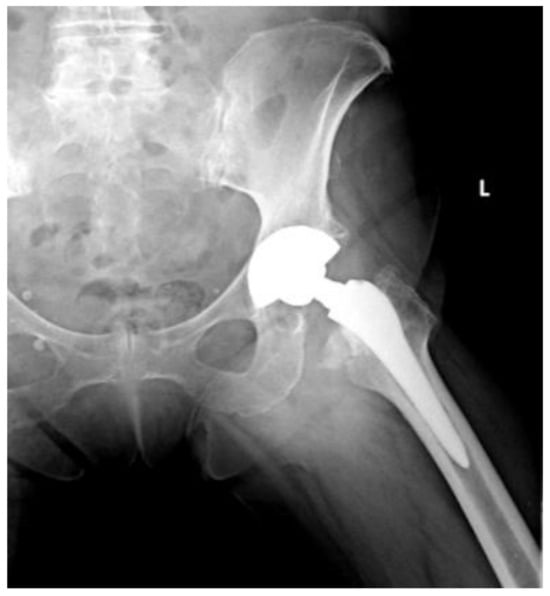

Of the 84 patients enrolled in this study, 44 patients (52.4%) received a THA with a straight stem (group A) (Figure 1 and Figure 2) and 40 patients (47.6%) received a THA with an anatomical stem (group B) (Figure 3 and Figure 4).

Figure 4.

Axial X-rays view of a total hip arthroplasty with anatomical stem (group B).